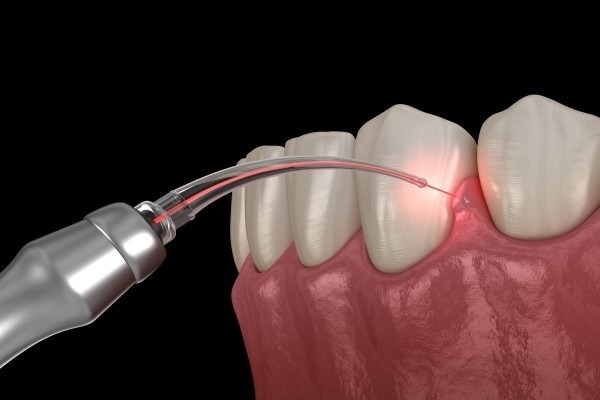

3. Laser Dentistry – Precision Without the Pain

Traditional drills and scalpels often cause anxiety. However, with laser dentistry, many procedures are now painless and stress-free.

- Gum reshaping

- Cavity preparation

- Teeth whitening

- Treating gum disease

Because lasers are precise and minimally invasive, they reduce bleeding, swelling, and discomfort. This is why many patients describe laser dentistry in Vizag, Vizianagaram, and Srikakulam as one of the best advances in dental care.

At V Dental Care, our focus on painless dental treatment in Vizag has helped countless patients overcome dental fear and seek timely care.